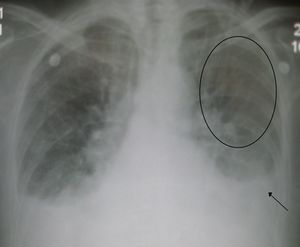

فشل أو قصور الجانب الأيسر من القلب

الجانب الأيسر هو المسؤول عن استقبال الدم المحمل بالأكسجين من أوردة الرئتين ثم ضخه إلى جميع أعضاءالجسم ومن ثم فالفشل في الجانب الأيسر يؤدي إلى تراكم الدم في الأوعية الدموية للرئتين والاحتقان فيهما فيؤدي إلى أعراض مرتبطة بيهما وقد يؤدي هذا التراكم أو الأحتقان إلى خروج السوائل من أوعية الرئتين إلى حجرات التنفيس، ويسبب وذمة الرئة. كما يؤدي فشل الجانب الايسر إلى فقر الدم الموزع إلى الأنسجة لفشله في ضخه لأعضاء الجسم فتعاني من نقص في أمداد تلك الأنسجة بالموادالغذائية والأكسجين. و أهم الأعراض هي:

علامات فشل الجانب الأيسر: ترتبط بفشل عمل القلب كمضخة وقلة الدم المضخوخ للأنسجة. مما يؤدي إلى ضعف النبض, هبوط في الضغط الانقباضي وزيادة سرعة ضربات القلب وبرودة الأطراف وقلة ادرار البول والشحوب. كما يرتبط قصور الجانب الايسر باحتقان الرئتين وتجمع السوائل فيهما.